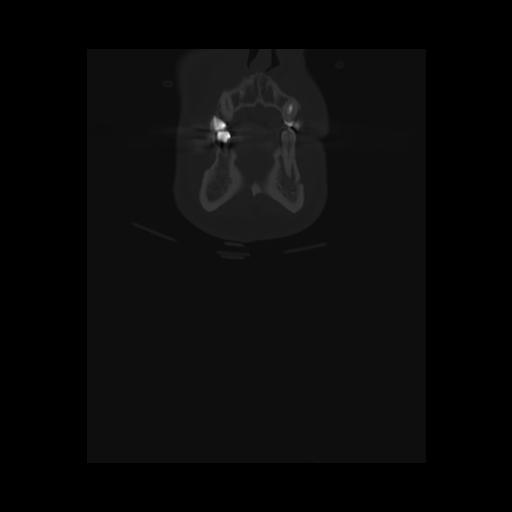

16 HUESO,,Coronal,2.000,HUESO,Coronal,